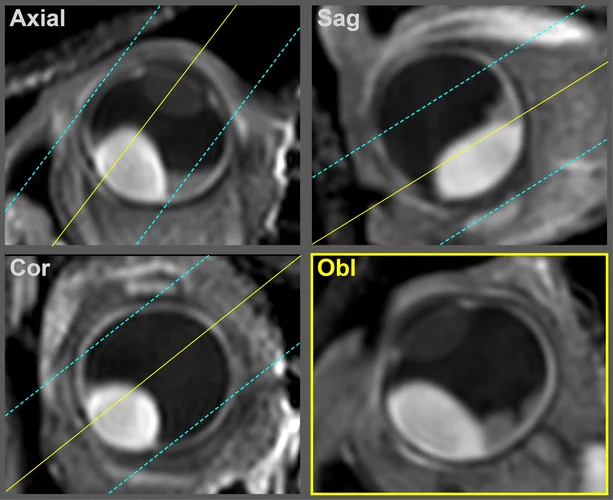

Obl

The orientation of multi-slice scans is tailored to the location and geometry of the tumour. It is typically perpendicular to the sclera and chosen such that the lesion and associated pathology are visualized in one slice.

For patients with complex pathology, e.g. both retinal detachment and optic nerve invasion, we perform these scans twice with different orientations.